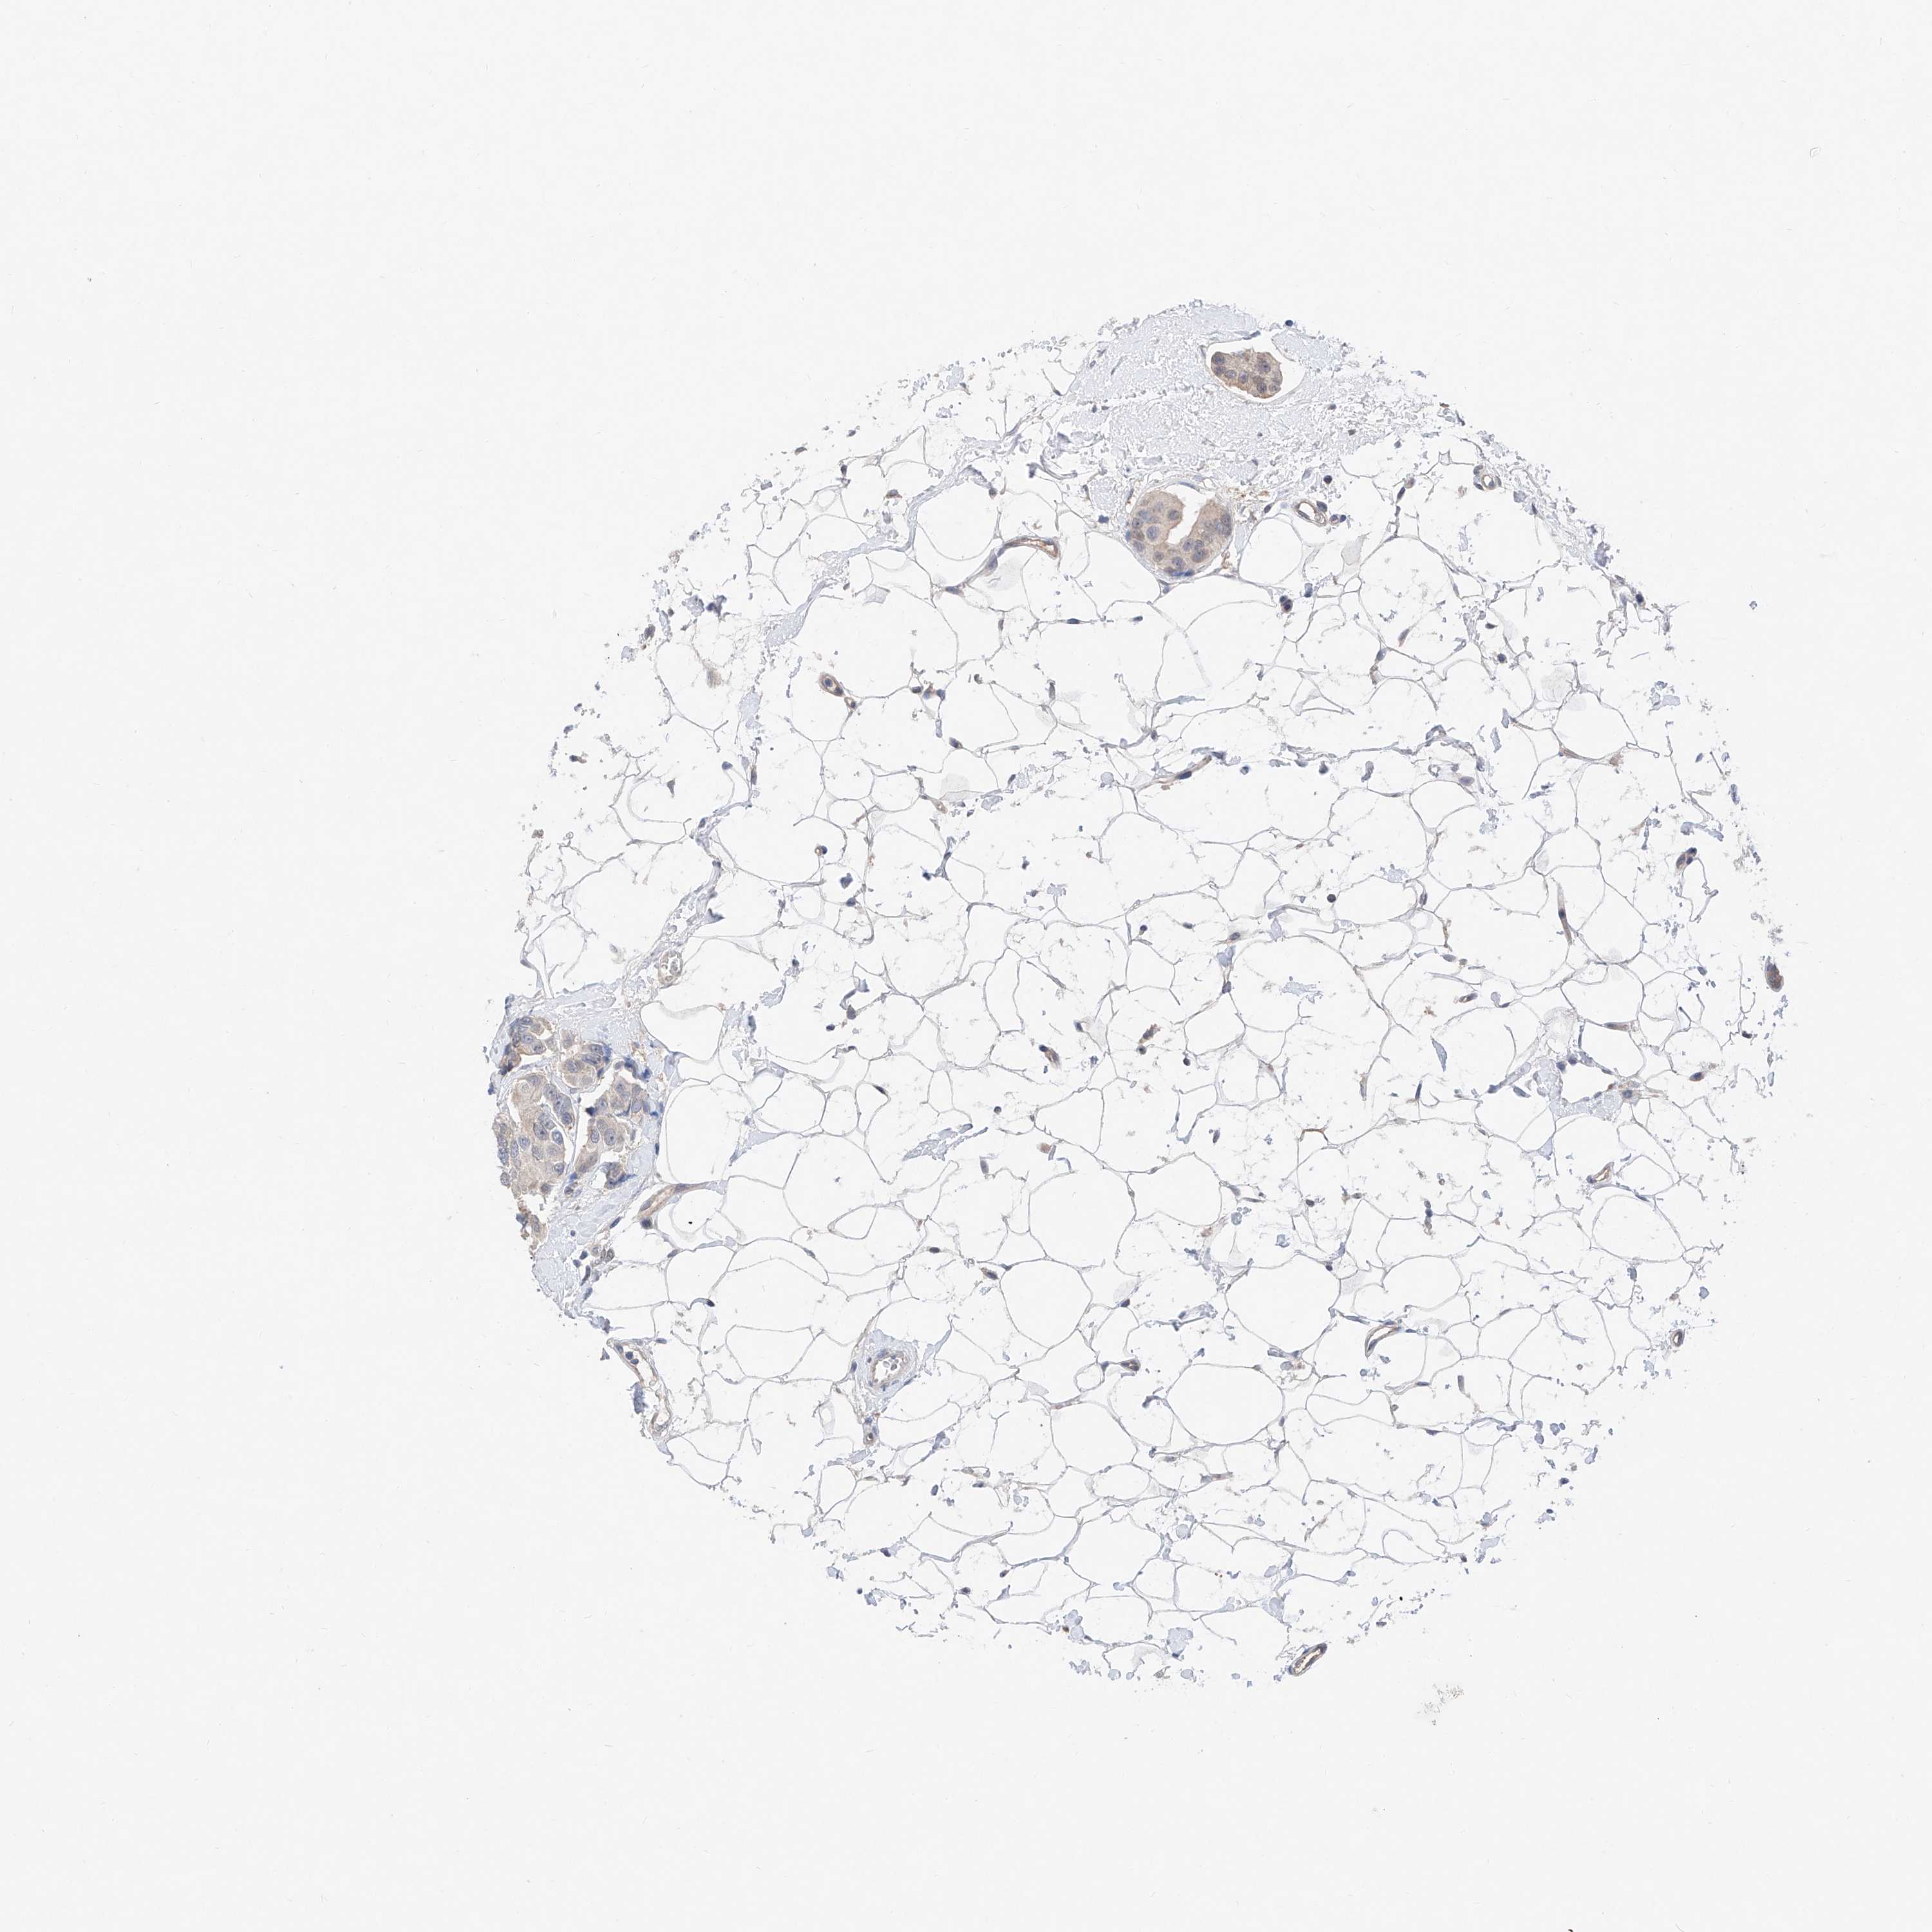

BRCA TCGA BRCA VALIDATION PROTEIN EXPRESSION

ANTIBODIES

AND

VALIDATION